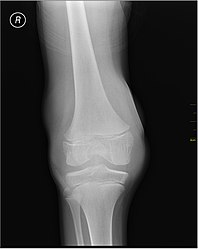

Joint capsule

Muscle and joint haemorrhages – or haemarthrosis – are indicative of haemophilia,[7] while digestive tract and cerebral haemorrhages are also germane to other coagulation disorders.

Repeated bleeds into a joint capsule can cause permanent joint damage and disfigurement resulting in chronic arthritis and disability. Joint damage is not a result of blood in the capsule but rather the healing process. When blood in the joint is broken down by enzymes in the body, the bone in that area is also degraded, this exerts a lot of pain upon the person afflicted with the disease.[8][9][10]